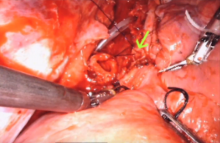

A 15-year-old girl initially presented with complete obstruction of her left main stem bronchus with complete atelectasis of the left lung. She had been like this for one year. The left main stem was cleared with a bronchoscope and the lung re-expanded. The diagnosis was a granular cell tumor of the distal left side of the trachea and left main stem bronchus. She and her parents requested a minimally invasive approach. Initially, the authors thought this would not be possible. However, with continued improvement in minimally invasive technique, they changed their opinion. They prepared for the procedure by performing the operation on a cadaver. Using the lessons learned and knowledge gained from this cadaveric simulation, they then performed the procedure on the patient. The patient did well, and she returned to school two weeks following the procedure. This video demonstrates the cadaveric procedure as well as the carinal resection and reconstruction.